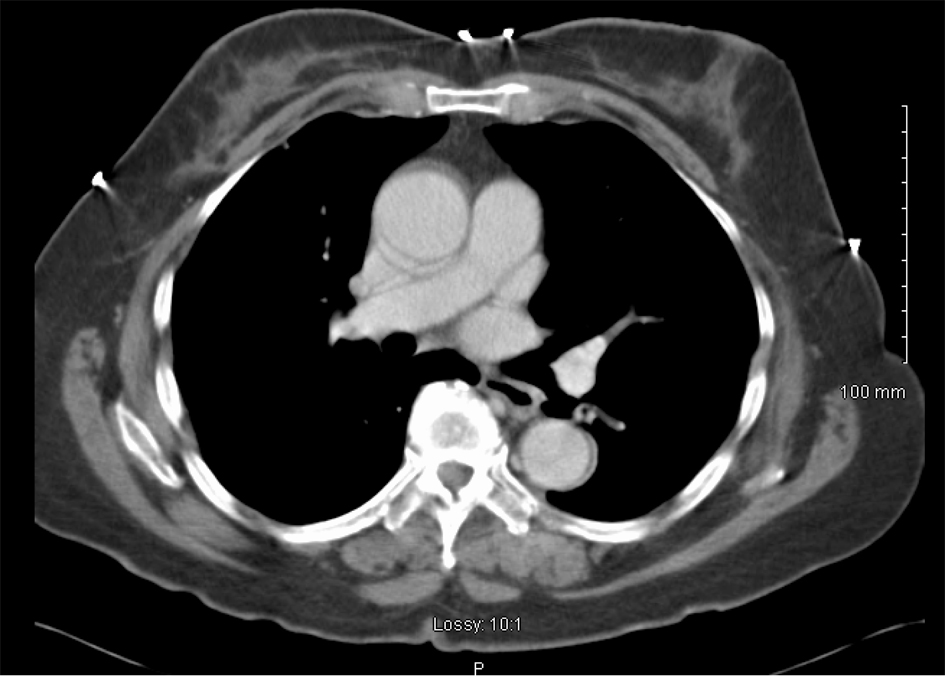

She was treated with 6 cycles of carboplatin and paclitaxel at an AUC of 6 and 175 mg/m2 respectively, with excellent biochemical and clinical response. Her CA-125 level decreased to 3 IU/mL and follow-up CT chest showed complete resolution of pleural disease including the pleural nodules (Fig. 5). She continues to have surveillance visits and remains disease-free 5 years later. Her chest imaging remains normal and serum CA-125 level remains at 3 U/mL.

![]() Click for large image | Figure 5. CT scan image after treatment demonstrating complete resolution of pleural effusion and nodularity. |